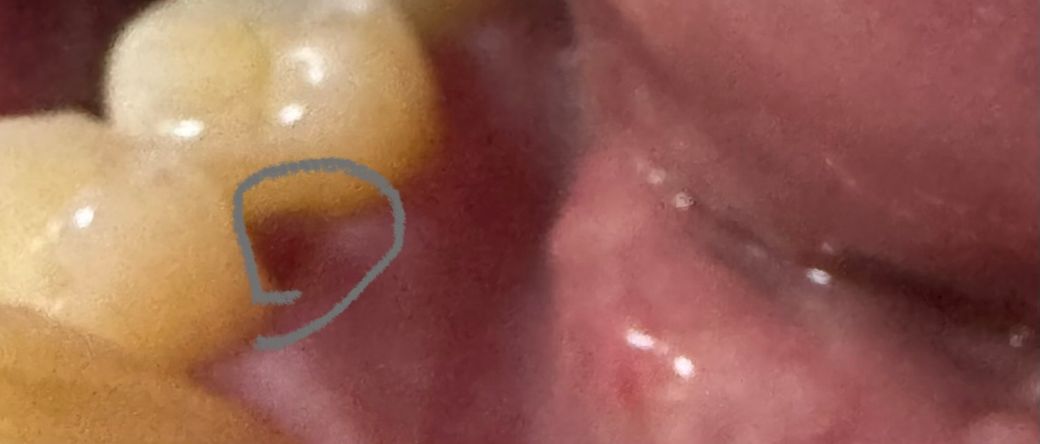

잇몸안쪽좀 봐주세요 잇몸안쪽치아사이 파임

사진속 앞니옆쪽에 안쪽으오 치아사이 동그라미 친 부분에

보면 바깥쪽은 잇몸이 괜찮은데 저 부분만 잇몸이 퇴축인지

잇몸살이 파여서 음식물 고기같은게 유난히 잘끼는데

• 1번 째 사진

• 안녕하세요. 최석민 치과의사입니다.

해당부위는 검진해도 잘 못보고 넘어갈 수도 있고요

치간유두부위 잇몸이 약간 퇴축된 상태인데 지금 특별히 염증이 있거나 통증이 있는게 아니라면 이상태에서 정기적으로 스케일링 받으면서 유지만 시켜줘도 됩니다

잇몸 이식이 적절한 부위는 아닙니다